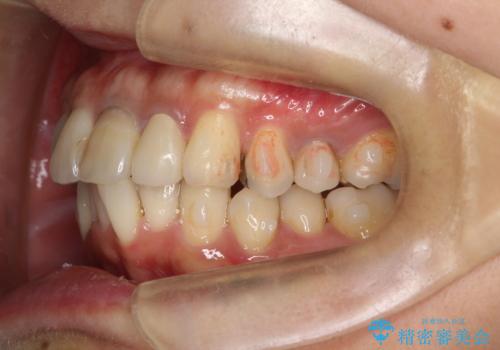

- 全体的なガタガタと前歯をきれいにしたいとのことで来院されました。

下の歯は重度のガタガタがあり、上の前歯は何本かが神経の治療がしてある状態でした。

インビザラインにて歯並びを整え、上顎の前歯にセラミックを装着する計画としました。